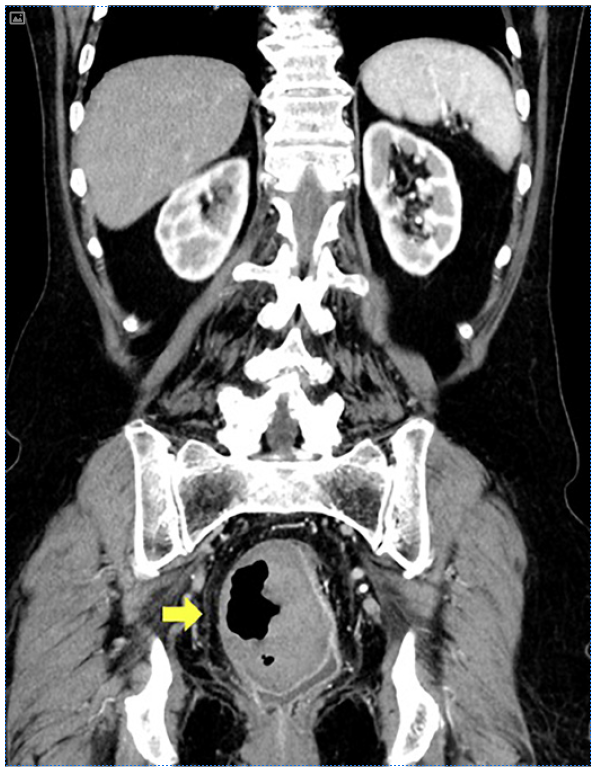

An abdominal and pelvic computerized tomography was performed, revealing an intramural collection containing hydroaeric levels in the right rectal wall, with a maximum diameter of 7 cm, compressing the rectal lumen (Fig. 2). The lower gastrointestinal bleeding and endoscopic findings were thus interpreted in the context of a rectal mural hematoma, communicating with the rectal lumen. The patient under-went conservative treatment, with complete reabsorption of the hematoma 2 months after surgery, which was confirmed by cross-sectional imaging and colonoscopy (Fig. 3).

Fig. 2 Abdominal and pelvic computerized tomography revealing an intramural collection containing hydroaeric levels in the right rectal wall, with a maximum diameter of 7 cm, compressing the rectal lumen.